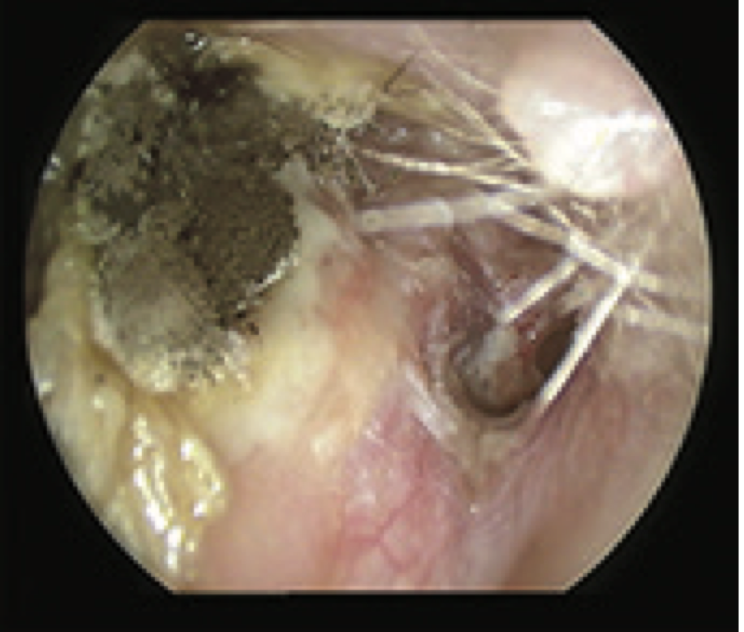

4

Q

What is this?

A

Fungal ear II

- Aspergillus niger

- fungal collection in mastoid cavity

-anterior inferior TM perforation